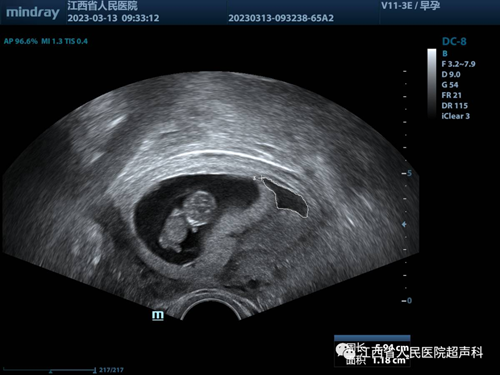

随着孕检的规范和普及,许多早孕期宝妈会进行彩超产检,很多宝妈经常会拿到诊断有“孕囊旁积液”的彩超报告,那么这个“孕囊旁积液”到底是什么东西?对妊娠囊有没有危害?该怎么处理?下面为大家一一解答。

随着人们对健康的重视,许多宝妈一旦发现怀孕就会去做B超检查,有的时候会发现孕囊周围存在液性暗区,其实这个液性暗区就是孕囊旁的液体,一般是怀孕早期孕囊周边的出血或称为积液。

这种情况多属于植入性出血,说明孕囊与宫壁之间的缝隙里面有液体,大多数原因是孕囊在子宫中种植不稳,使得孕囊与子宫壁有些许剥离,导致孕囊周边积液,其量通常与出血量呈正相关。少量的孕囊旁积液绝大多数可以通过自身进行吸收,如积血量比较大,未被自身吸收,则可由阴道排出。